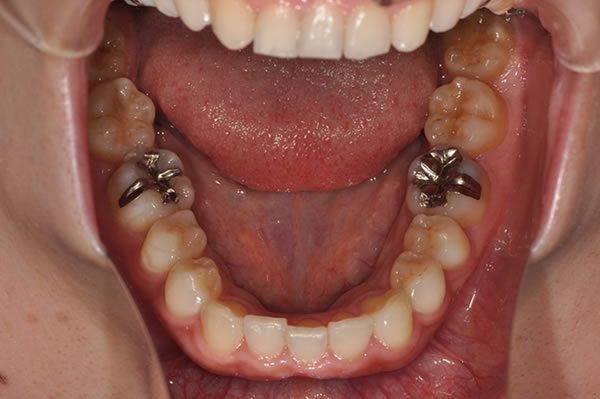

上顎前突症の治療例

上顎前突症(出っ歯)の矯正症例 ケース01

上顎前突症(出っ歯)の矯正症例 ケース02